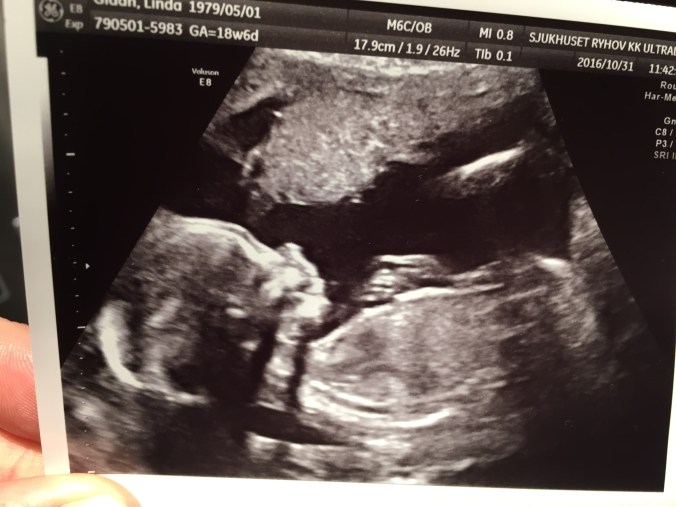

Du är hemlighetsfull och busig- vad jag än tittar på för skrönor om vad bebisen ska vara för kön så ligger du typ mitt i. Du har en medelpuls på ca 140-142, vilket är varken högt (”flicka”) eller lågt (”pojke”), magen ändrar form titt som tätt så ena stunden är den jättebred (”flicka”) och andra mer smalputig (”pojke”).